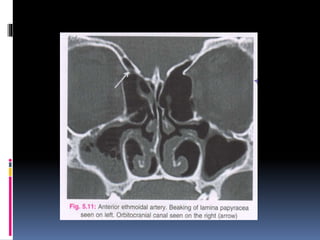

 2-3 mm behind the bulla, the anterior ethmoidal artery is seen

as a classical ‘BEAKING’ of the medial orbital wall.

 Once branching from the ophthalmic artery, it accompanies

the nasociliary nerve through the anterior ethmoidal canal to

supply the anterior and middle ethmoidal cells, frontal sinus,

and anterosuperior aspect of the lateral nasal wall.

 Ethmoidal artery is an important anatomical structure to be

recognized during endoscopic sinus surgery.

 The anterior ethmoidal artery is the best landmark for the

roof of the ethmoid sinus or the anterior base of the skull.